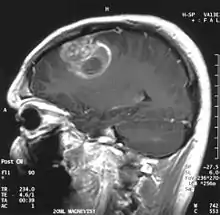

Coronal MRI with contrast of a glioblastoma in a 15-year-old male | |